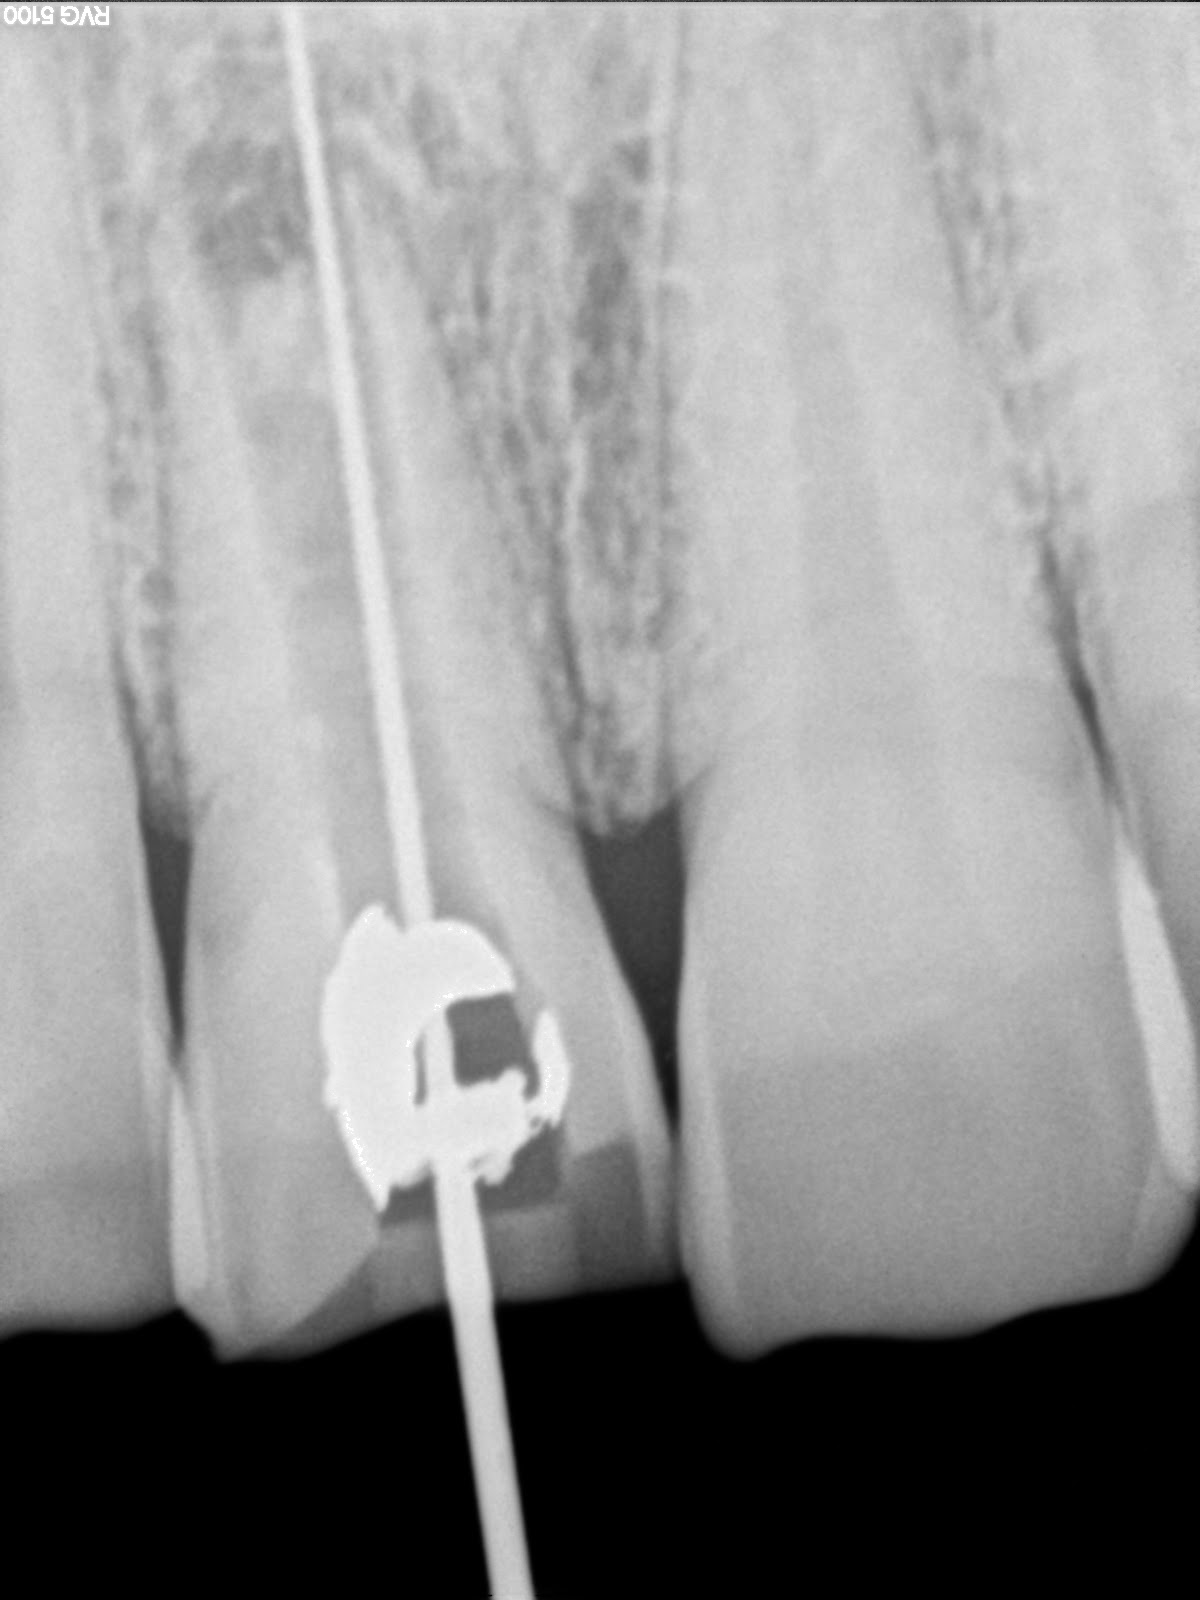

Endodontics Re rootcanal treatment with open apex central incisor Open Apex Tooth Definition immature tooth with an open apex is encountered by a clinician from time to time. the second factor is the apex diameter. an ‘open apex’ is found as a developmental stage in the permanent and primary dentition, as a sequel to pulp. Proper diagnosis and treatment planning. in children, where the tooth apex is open, the. Open Apex Tooth Definition.